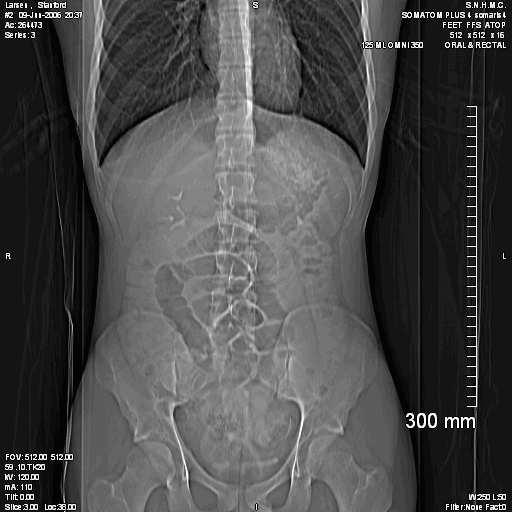

2006 06 09 - Stanford's first CT scan

0105.jpg